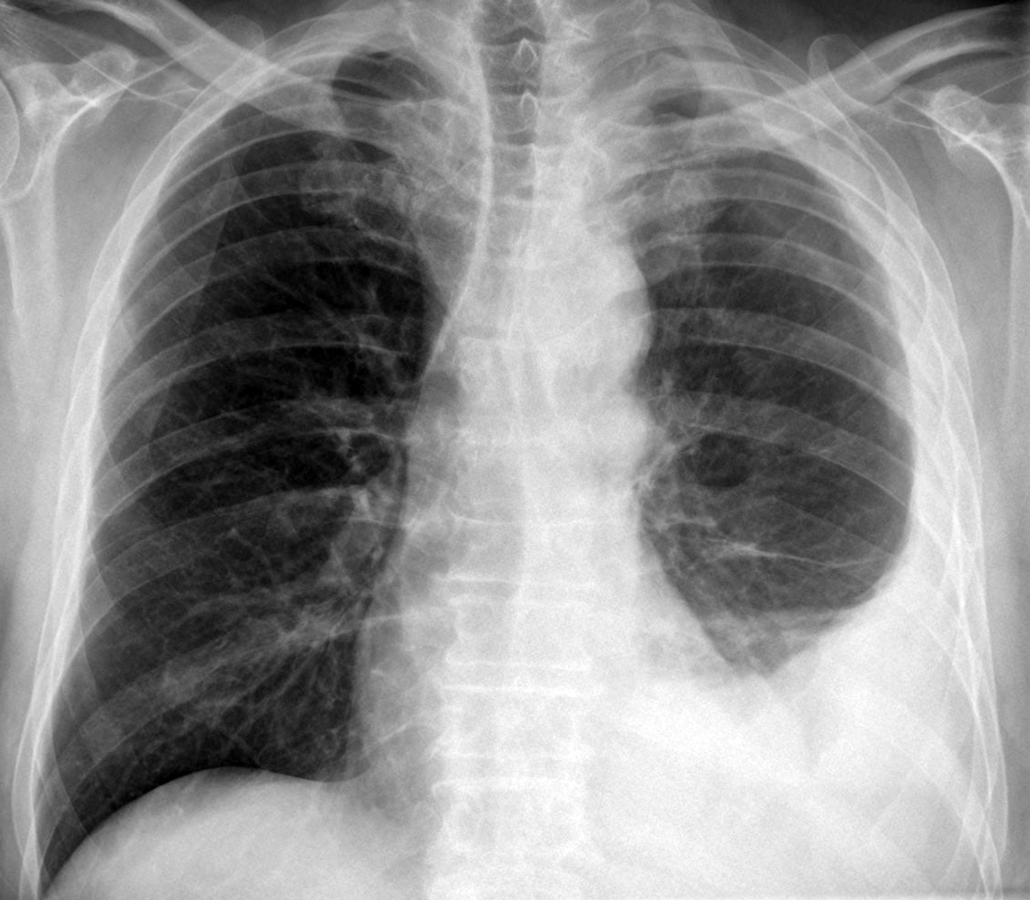

Pleuramesotheliom im Röntgenbild des Thorax: Pleuraverdickung und -erguß links. Pleuramesotheliom im Röntgenbild des Thorax: Pleuraverdickung und -erguß links. © wikipedia/Hellerhoff (CC 3.0)